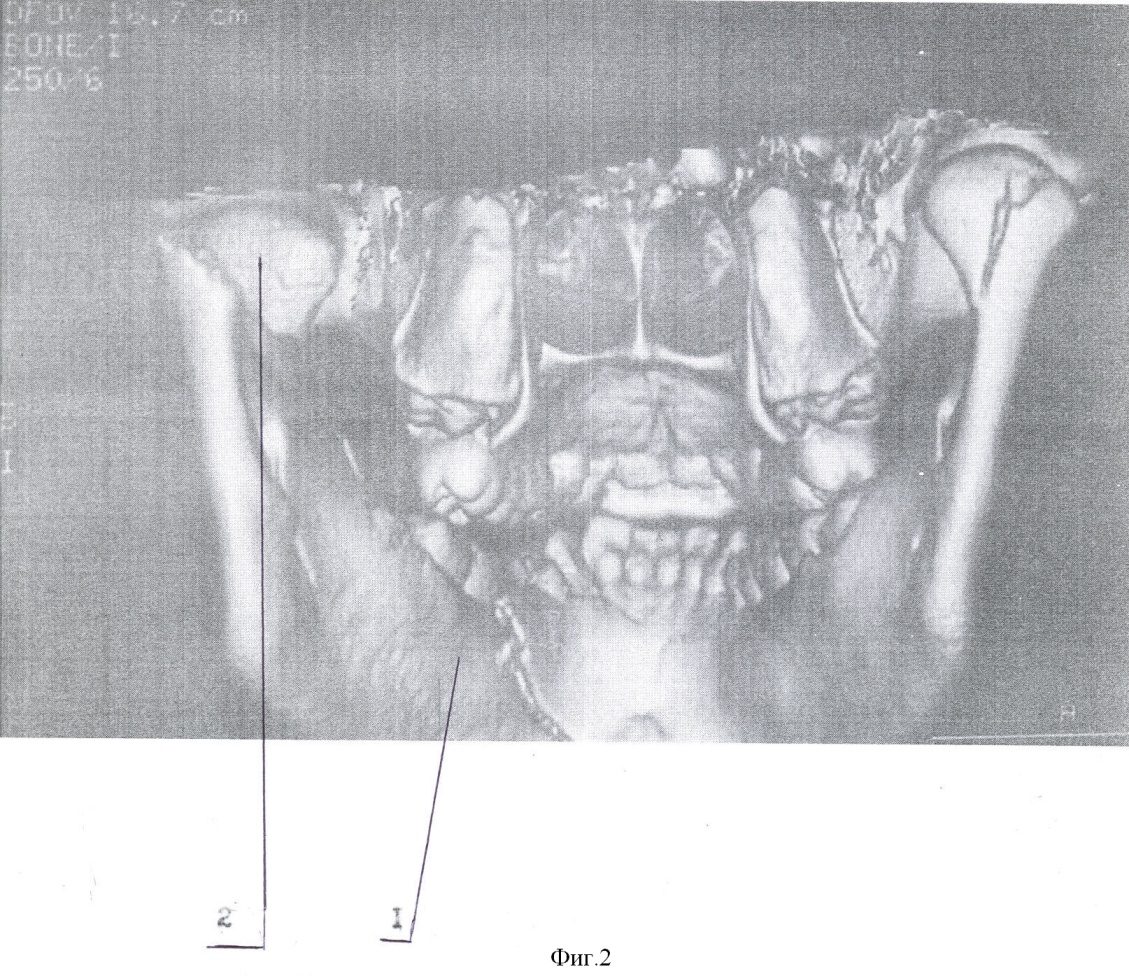

Способ осуществляют следующим образом. Типичным доступом через разрез кожи в подчелюстной области, окаймляющим угол нижней челюсти, осуществляют послойный доступ к линии перелома поднадкостнечно по латеральной поверхности ветви. Вывихнутый диссектором малый фрагмент вместе с суставной капсулой выводят в вырезку. Суставную капсулу рассекают вперед на 0,3-0,5 см. Отломок суставного отростка освобождают от суставной капсулы и выводят из раны. Фиброзные наложения раневых поверхностей костей удаляют. После оценки состояния отломка к участку, свободному от суставной поверхности, по заднему краю фиксируют микропластину (Т, Н, Х, L, Y-образной формы). Свободный конец микропастины изгибают для плотного прилегания к большему фрагменту по задней и латеральной поверхности ветви. Из суставной капсулы формируют ложе в суставной впадине. Малый фрагмент с подготовленной микропластиной устанавливают в ложе в анатомическом положении. Суставную капсулу над суставным бугорком укрепляют узловыми швами ПДС 4/0. Большой фрагмент репонируют на установленную в ложе конструкцию. Свободный конец микропластины фиксируют к заднелатеральной поверхности большего фрагмента микрошурупами. Осуществление способа и результат продемонстрированы на чертежах 1-8: фиг.1 – компьютерная томограмма (реконструкция) нижней челюсти, левая боковая; фиг.2 – компьютерная томограмма (реконструкция) нижней челюсти, вид сзади; фиг.3 – компьютерная томограмма (реконструкция) нижней челюсти, вид косо сзади; фиг.4 – собранная конструкция, вид сзади; фиг.5 – собранная конструкция, вид спереди; фиг.6 – компьютерная томограмма (реконструкция), вид спереди, после операции; фиг.7 – компьютерная томограмма (реконструкция) нижней челюсти, левая боковая, после операции; фиг.8 – компьютерная томограмма (реконструкция) нижней челюсти, левый суставной отросток, вид изнутри, после операции: где 1 – нижняя челюсть, 2 – отломок суставного отростка, 3 – титановая микропластина, 4 – микрошуруп, 5 – дренажная трубка.

Пример. Больной П., 14 лет поступил в отделение челюстно-лицевой хирургии ДККБ 20.04.07 г. с диагнозом: травматический тройной перелом нижней челюсти; перелом – вывих головки суставного отростка слева, перелом суставной головки справа без смещения, косой центральный перелом тела нижней челюсти со смещением (фиг. 1, 2, 3). 23.04.07 г. под общим обезболиванием выполнено оперативное вмешательство – открытая репозиция, металлоостеосинтез суставной головки слева Т-образной микропластиной, открытая репозиция, металлоостеосинтез косого перелома тела нижней челюсти двумя параллельными минипластинами. Типичным доступом через разрез кожи в подчелюстной области слева, окаймляющим угол нижней челюсти 1, осуществлен послойный доступ к линии перелома поднадкостнечно по латеральной поверхности ветви нижней челюсти. При помощи диссектора малый фрагмент мобилизован и вывихнут в вырезку вместе с суставной капсулой. Суставная капсула рассечена вперед на 0,5 см. Отломок суставного отростка 2 освобожден от суставной капсулы и выведен наружу. Фиброзные наложения на раневых поверхностях фрагментов удалены. По заднему краю отломка, по поверхности, свободной от суставной, при помощи микрошурупов 4 фиксирована Т-образная титановая микропластина 3, изогнутая для плотного прилегания к заднелатеральной поверхности большего фрагмента (фиг. 4, 5). Суставная капсула перемещена и расправлена в суставной ямке. В образованное ложе уложена конструкция в анатомическом положении. На края суставной капсулы над суставным бугорком наложены 2 узловых шва ПДС 4/0, обеспечивающие плотный охват отломка. Больший фрагмент репонирован на установленную конструкцию. Свободный конец микропластины 4 после небольшой коррекции изгиба фиксирован к заднелатеральной поверхности большего фрагмента микрошурупами 3. Рана послойно ушита с оставлением активного дренажа 5. Подчелюстным разрезом осуществлен послойный доступ к линии перелома тела нижней челюсти. Произведена типичная репозиция костных отломков, остеосинтез двумя параллельными минипластинами. Рана послойно ушита.

В послеоперационном периоде проводилась иммобилизация челюсти при помощи шин Васильева с межчелюстными вытяжениями. На контрольно компьютерной томограмме (26.04.07 г., фиг. 6, 7, 8) выявлено удовлетворительное стояние костных отломков. Больной выписан 4.05.07 г на дальнейшее амбулаторное лечение.